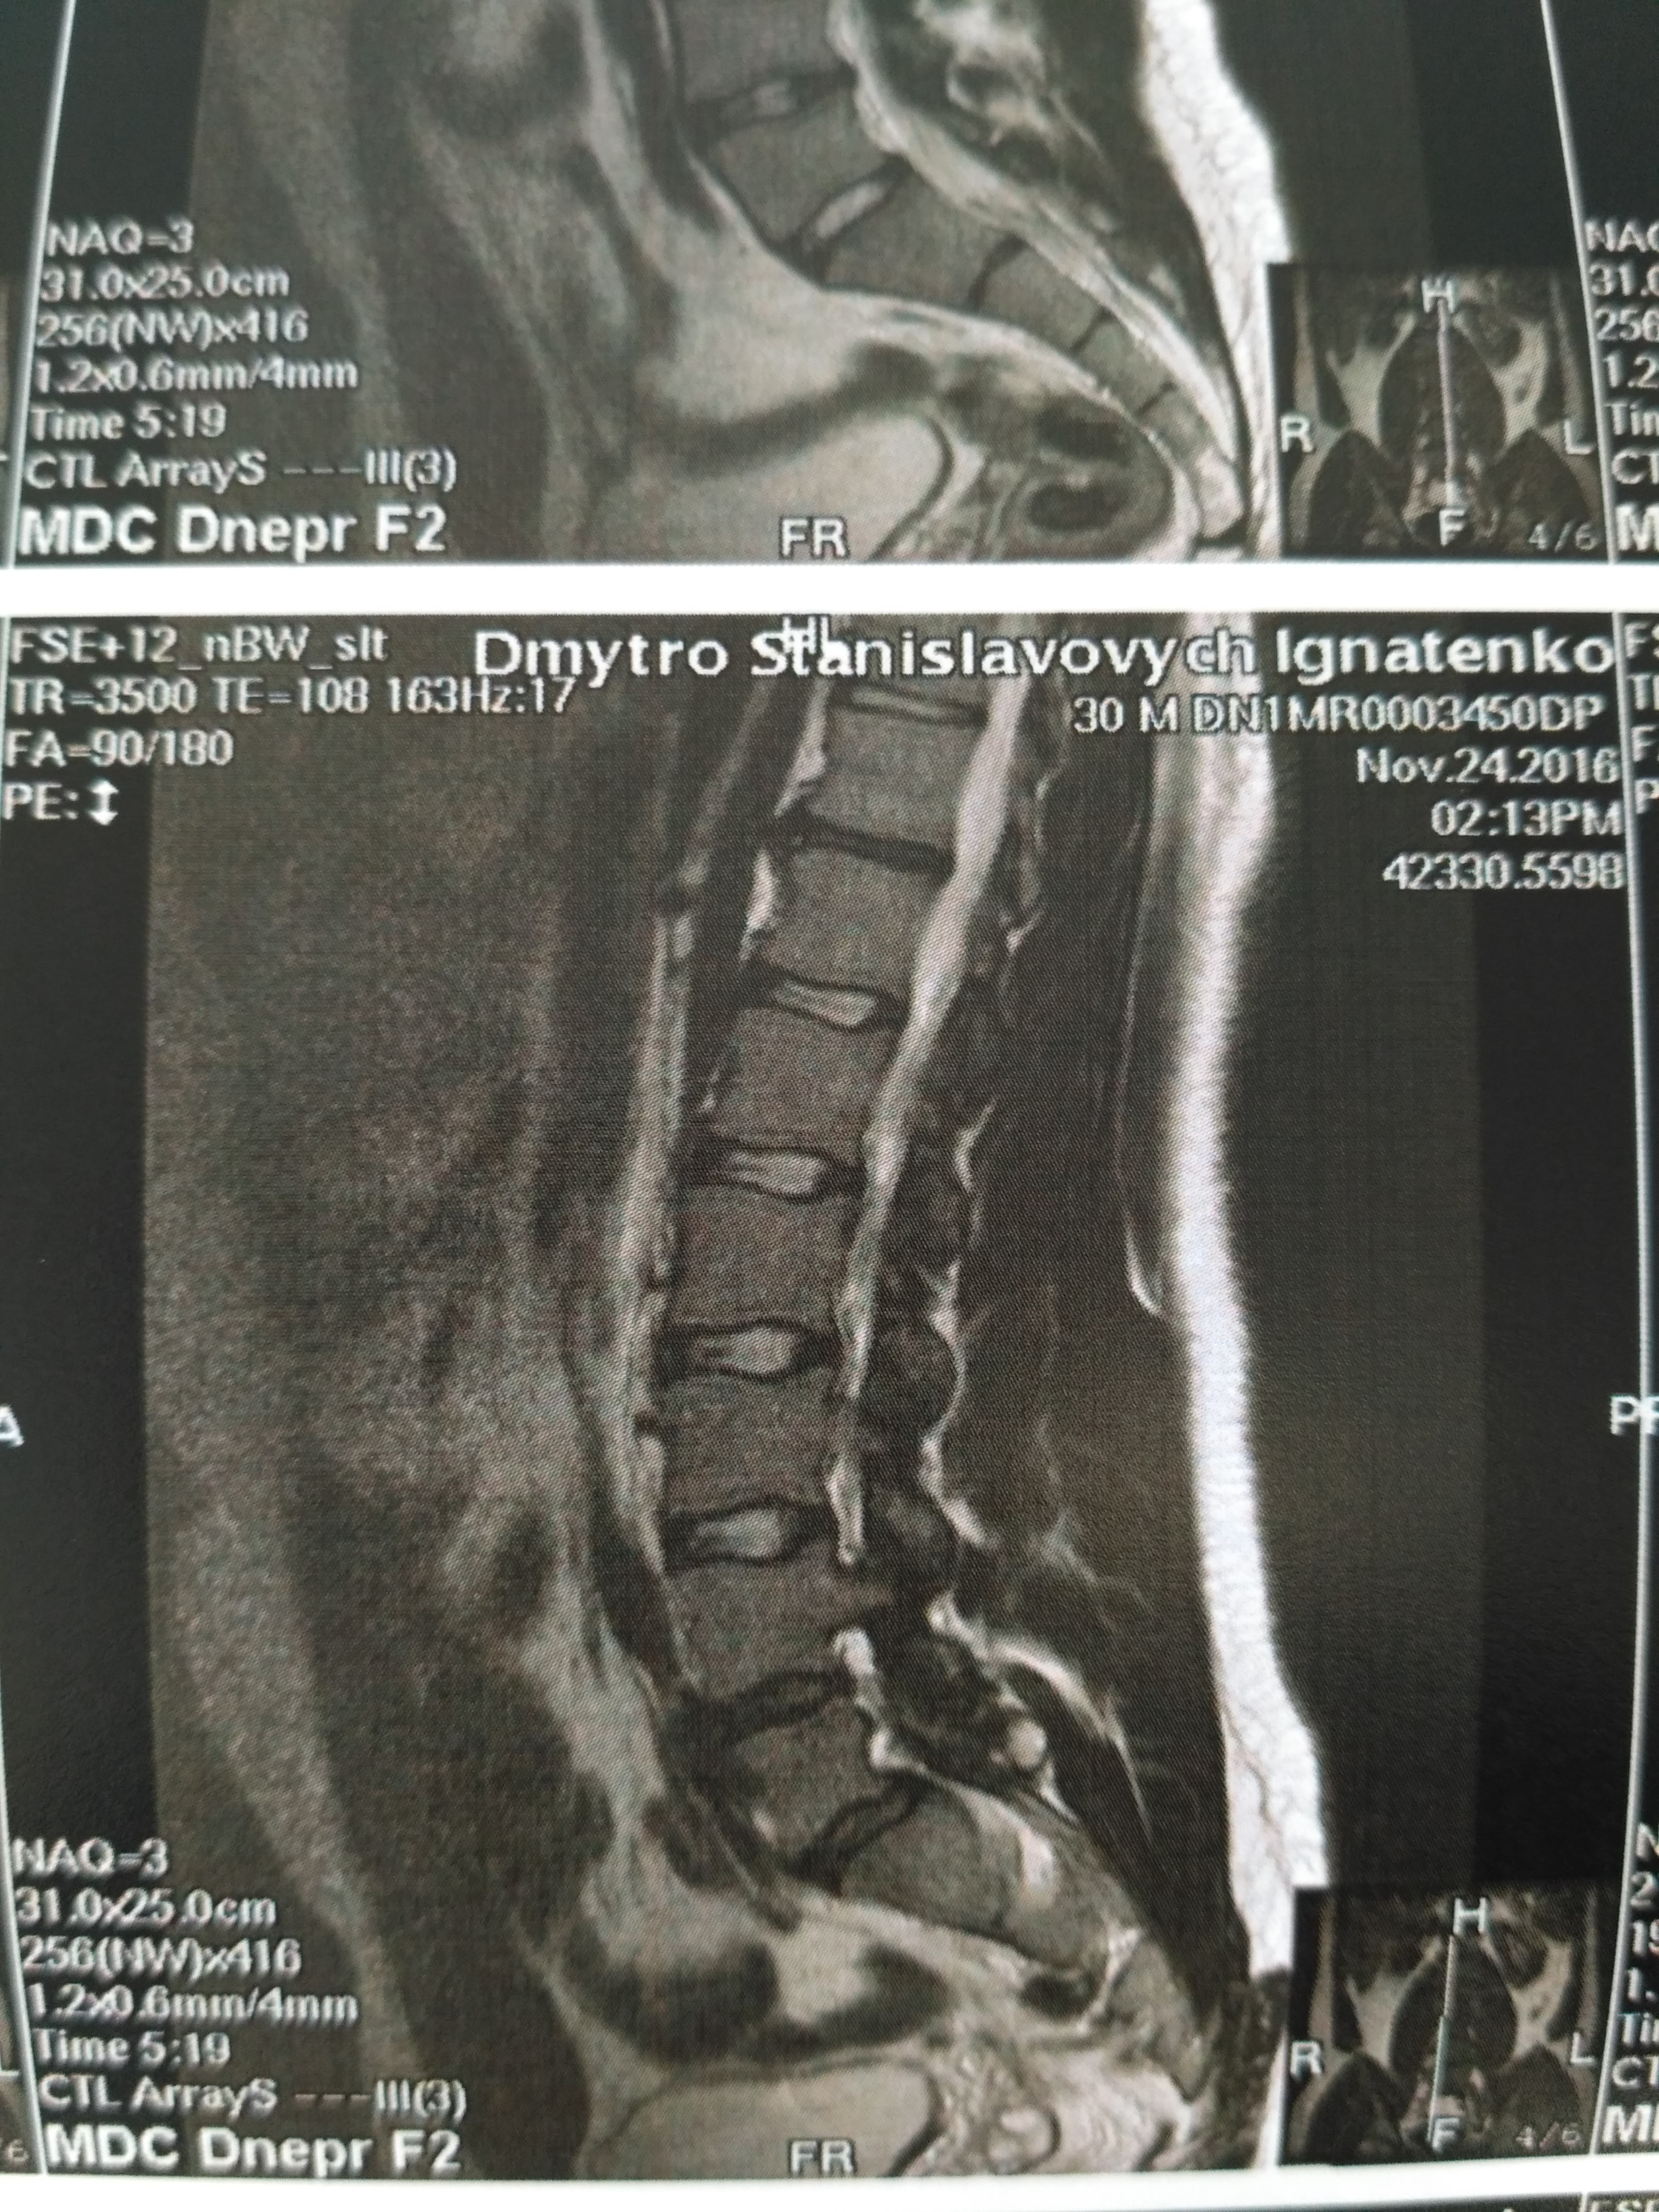

Тренировки с межпозвоночной грыжей.